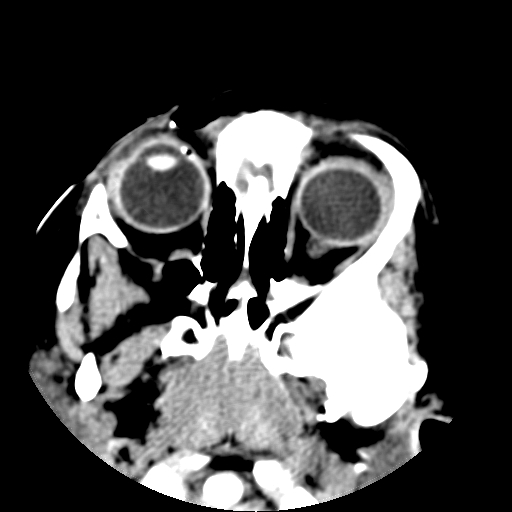

以下是引用深泽交通医院在2009-10-16 8:25:00的发言:[br]右眼环出血伴异物

以下是引用卜一在2009-10-16 15:01:00的发言:[br]右眼球挫裂伤伴异物!

以下是引用拾荒者在2009-10-17 18:38:00的发言:[br]鼻面部皮下积气,右侧睑缘及眼球壁高密度异物影,左侧眼球壁晶状体内侧缘处是圆形低密度影。低密度异物?应提请眼科医生注意。